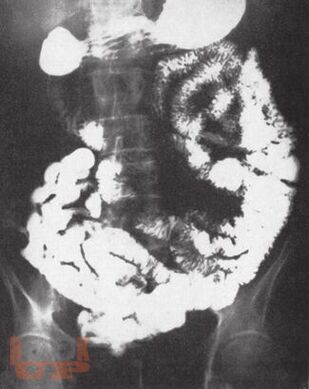

Монография является пятой и заключительной книгой серии «Хроническая абдоминальная боль». Автор представила основные причины боли при заболеваниях других органов и систем, которые могут проявляться абдоминальной болью. Особое внимание уделено патогенезу, клинической характеристике и дифференциальной диагностике болевого синдрома, а также лечению.